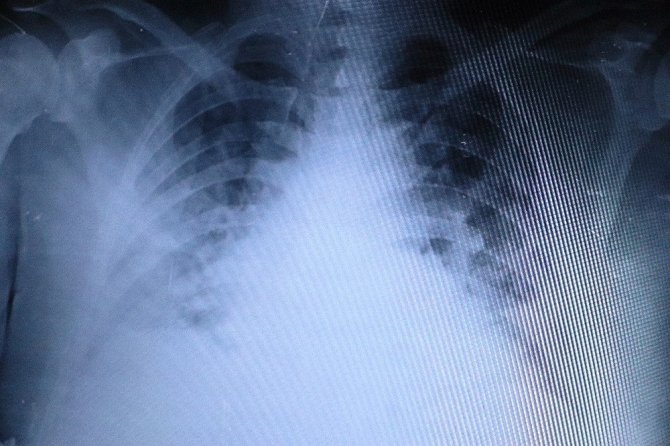

"Aşı olan ile olmayan evli çiftin akciğerlerindeki inanılmaz fark"

Bir evli çiftin akciğer filmlerini inceleyen Özkaya, "Size bir evli çiftin akciğer filmlerini göstermek istiyorum. İkisi de 50 yaşında. Çiftlerden biri sağlıkçı olduğu için aşılandı, diğeri ise aşı olmadı. Bu kadın hastamız kendisi sağlıkçı olduğu için Covid-19 pozitif olmasına rağmen akciğerlerinde hiçbir lezyon yok. Yine aynı yaştaki eşi aşı yapılmadığı için akciğerlerinde Covid-19 lezyonlarıyla uğraşıyoruz. İkisi de şu an korona servisinde yatıyor. Aşı olmayanın akciğerleri çok ciddi anlamda harap olmuşken aşı olan bir hastamızın testi pozitif olmasına rağmen akciğerleri tertemiz. Aile içi bulaş oldukça fazla. Özellikle bugün gelen ailenin akciğerlerine bakacak olursak, annenin ve babanın akciğerleri hafif tutulum sergilerken, 29 yaşındaki oğullarının akciğerlerinde aşırı bir tutulum var. Hasta profilleri biraz genç tarafa doğru kayıyor" şeklinde konuştu.